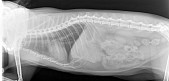

3-ий день нет аппетита, настроения, пьет в норме, писает нормально, но стул последний раз был позавчера вечером на вид обычный, правильной консистенции и цвета. Рвоты и слюней нет. Постоянно спит, слабый и аппатичный. Полторы недели назад зацепил коготь на задней лапе и вырвал, лунку я мазала левомеколем и олазолем и там уже затянулось и растет новый коготь. Вчера свозила к ветеринару, температура оказалась повышенная 41.3, при аскультации врач услышала хрипы, мышечной слабости нет, боли при пальпации нет, область глотки не отечна, проприорецепция сохранена, ВСО розовые, СНК 2 сек, истечений из глаз и носа нет. Сделали рентген, поставили мочегонное, антибиотик, жаропонижающее (Фуросемид 2.0 мл,Синулокс 0.3мл, Кетофен 1мл) и взяли кровь на анлиз.

В клинике пока не сделали окончательный диагноз, предварительный у меня написано в карте: Отек легких. Неисключенный диагноз: ГКМП, пневмония, неоплазия.

Рентген прилагаю.